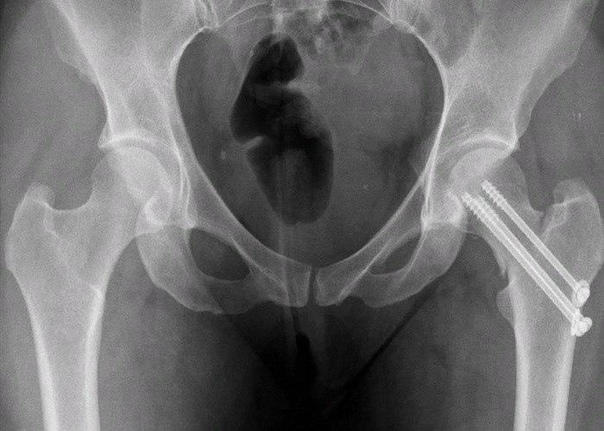

ΠΒ ΠΠ»ΠΈΠ½ΠΈΡΠ΅ΡΠΊΠΎΠΌ Π³ΠΎΡΠΏΠΈΡΠ°Π»Π΅ Π½Π°Β Π―ΡΠ·Π΅ ΠΌΡΒ Π²ΡΠΏΠΎΠ»Π½ΡΠ΅ΠΌ Π½Π΅ΡΠΊΠΎΠ»ΡΠΊΠΎ Π²ΠΈΠ΄ΠΎΠ² ΠΎΠΏΠ΅ΡΠ°ΡΠΈΠΉ. ΠΒ Π·Π°Π²ΠΈΡΠΈΠΌΠΎΡΡΠΈ ΠΎΡΒ Π²ΠΎΠ·ΡΠ°ΡΡΠ° ΠΈΒ ΠΎΠ±ΡΠ°Π·Π° ΠΆΠΈΠ·Π½ΠΈ ΠΌΡΒ Π·Π°ΠΌΠ΅Π½ΡΠ΅ΠΌ ΠΈΠ»ΠΈ Π²Π΅ΡΡ ΡΡΡΡΠ°Π² ΠΏΠΎΠ»Π½ΠΎΡΡΡΡ (Π΄Π»Ρ Π±ΠΎΠ»Π΅Π΅ Π°ΠΊΡΠΈΠ²Π½ΡΡ ΠΏΠ°ΡΠΈΠ΅Π½ΡΠΎΠ²), Π»ΠΈΠ±ΠΎ ΡΠΎΠ»ΡΠΊΠΎ ΡΠ»ΠΎΠΌΠ°Π½Π½ΡΡ ΡΠ΅ΠΉΠΊΡ ΠΈΒ Π³ΠΎΠ»ΠΎΠ²ΠΊΡ (Π΄Π»Ρ ΠΌΠ°Π»ΠΎΠΏΠΎΠ΄Π²ΠΈΠΆΠ½ΡΡ ΠΏΠ°ΡΠΈΠ΅Π½ΡΠΎΠ²). Π Π°Π·ΡΠ΅Π· Π²Β ΠΎΠ±Π»Π°ΡΡΠΈ ΡΠ°Π·ΠΎΠ±Π΅Π΄ΡΠ΅Π½Π½ΠΎΠ³ΠΎ ΡΡΡΡΠ°Π²Π° ΡΠΎΡΡΠ°Π²Π»ΡΠ΅Ρ ΠΎΠΊΠΎΠ»ΠΎ 15Β ΡΠΌ. ΠΠΏΠ΅ΡΠ°ΡΠΈΡ Π΄Π»ΠΈΡΡΡ ΠΎΡΒ 30Β Π΄ΠΎΒ 90Β ΠΌΠΈΠ½. ΠΡΠΎΠ²ΠΎΠΏΠΎΡΠ΅ΡΡΒ β ΠΎΡΒ 50Β Π΄ΠΎΒ 500Β ΠΌΠ». ΠΠΏΠ΅ΡΠ°ΡΠΈΡ Π²ΡΠΏΠΎΠ»Π½ΡΠ΅ΡΡΡ ΠΏΠΎΠ΄ ΡΠΏΠΈΠ½Π°Π»ΡΠ½ΠΎΠΉ Π°Π½Π΅ΡΡΠ΅Π·ΠΈΠ΅ΠΉ.

ΠΠ±Π΅ΡΠΏΠ΅ΡΠΈΡΡ ΠΏΡΠ°Π²ΠΈΠ»ΡΠ½ΡΠΉ ΡΡ ΠΎΠ΄ Π·Π° ΠΏΠ΅Π½ΡΠΈΠΎΠ½Π΅ΡΠΎΠΌ, ΡΠ»ΠΎΠΌΠ°Π²ΡΠΈΠΌ ΡΠ΅ΠΉΠΊΡ Π±Π΅Π΄ΡΠ°, Π² Π΄ΠΎΠΌΠ°ΡΠ½ΠΈΡ ΡΡΠ»ΠΎΠ²ΠΈΡΡ ΡΡΠ΅Π·Π²ΡΡΠ°ΠΉΠ½ΠΎ ΡΠ»ΠΎΠΆΠ½ΠΎ. ΠΠ°ΠΆΠ΅ Π΅ΡΠ»ΠΈ Π±ΡΠ»Π° ΠΏΡΠΎΠ²Π΅Π΄Π΅Π½Π° ΠΎΠΏΠ΅ΡΠ°ΡΠΈΡ ΠΈ Π²ΡΠ°ΡΠΈ ΠΏΡΠΈΠ²Π΅Π»ΠΈ ΠΊΠΎΡΡΠΈ Π² Π½ΠΎΡΠΌΠ°Π»ΡΠ½ΠΎΠ΅ ΠΏΠΎΠ»ΠΎΠΆΠ΅Π½ΠΈΠ΅ Ρ ΠΏΠΎΠΌΠΎΡΡΡ ΡΠΏΠ΅ΡΠΈΠ°Π»ΡΠ½ΡΡ Π²ΠΈΠ½ΡΠΎΠ², Π²ΡΠ΅Π³Π΄Π° Π΅ΡΡΡ Π²Π΅ΡΠΎΡΡΠ½ΠΎΡΡΡ ΠΎΡΠ»ΠΎΠΆΠ½Π΅Π½ΠΈΠΉ. ΠΡΠ»ΠΈ ΠΎΠΏΠ΅ΡΠ°ΡΠΈΡ Π½Π΅ Π΄Π΅Π»Π°ΡΡ, ΡΠΎ ΠΊΠΎΠ½ΡΠ΅ΡΠ²Π°ΡΠΈΠ²Π½ΡΠΉ ΠΌΠ΅ΡΠΎΠ΄ Π»Π΅ΡΠ΅Π½ΠΈΡ ΠΏΡΠ΅Π΄ΠΏΠΎΠ»Π°Π³Π°Π΅Ρ Π΄Π»ΠΈΡΠ΅Π»ΡΠ½ΡΠΉ Π»Π΅ΠΆΠ°ΡΠΈΠΉ ΡΠ΅ΠΆΠΈΠΌ Π² ΠΎΠΆΠΈΠ΄Π°Π½ΠΈΠΈ ΡΠΎΠ³ΠΎ, ΠΏΠΎΠΊΠ° ΠΊΠΎΡΡΡ ΡΡΠ°ΡΡΠ΅ΡΡΡ; ΡΡΠΎΠΊ ΠΎΠ±ΡΡΠ½ΠΎ ΡΠΎΡΡΠ°Π²Π»ΡΠ΅Ρ 3 ΠΌΠ΅ΡΡΡΠ°.